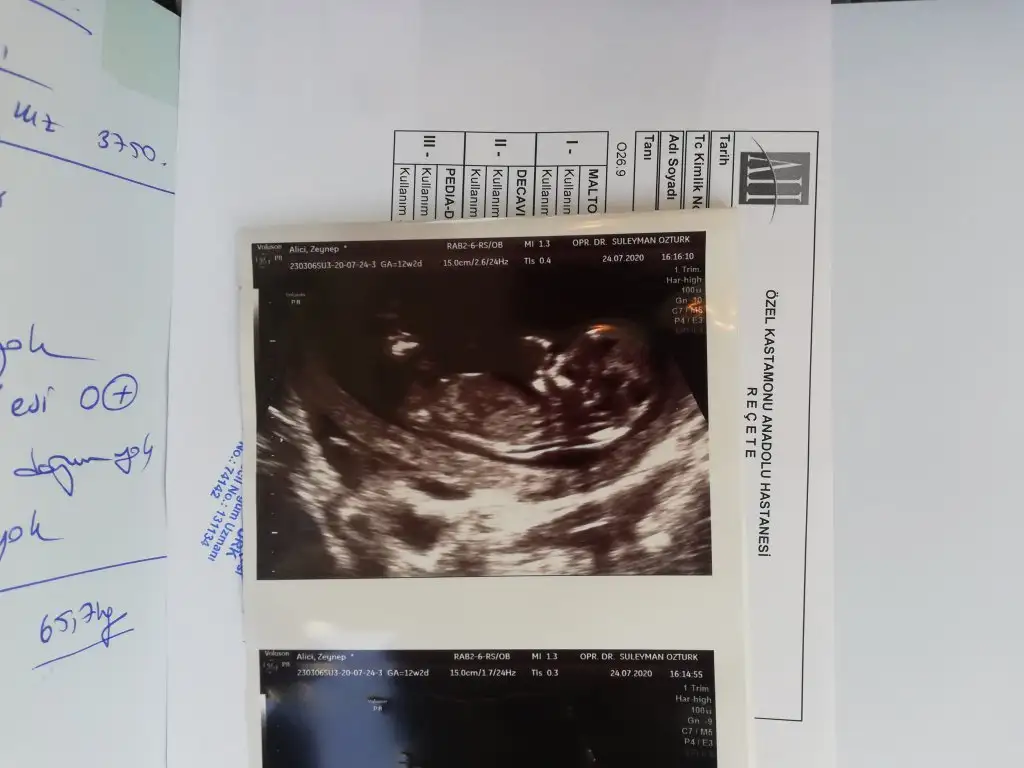

Nubu çok karanlık başka usg varmı erkek diyecem emin olamadımBenım ıcın de tahminde bulunur musunuz acaba 12+5 Haftadayım

Erkek gibi yinede 12-13 hafta usgde paylasinMerhaba ikra meyra benim bebişim içinde tahminde bulunurmusun rica etsem

Renkli olmayan USG paylaşınnub dediginiz neresi acaba bakiyom anlamiom